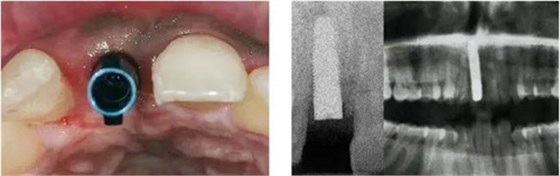

圖4、植入的種植體,初始穩(wěn)定性很好,由于骨缺損范圍大,選擇潛入式愈合。

圖5、種植體完全位于拔牙窩骨壁包圍的范圍內(nèi),距離唇側(cè)骨板至少2mm。

圖9、種植體植入5個月:種植體到唇側(cè)骨板的距離仍然大于2mm,這對于形成長期穩(wěn)的美學(xué)效果有很重要的作用。